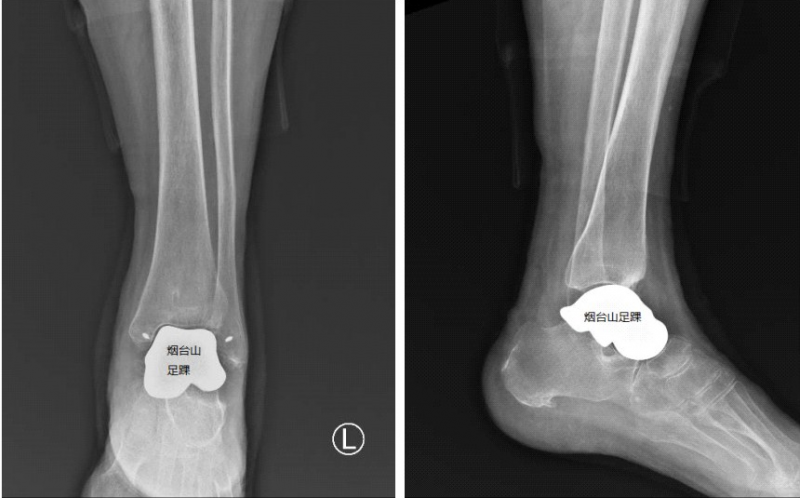

量身定制的3D打印全距骨假体。

为帮助患者解除疼痛,同时还能最大程度地保留关节的运动功能,曲文庆主任团队在对病例进行详细评估之后,决定实施3D打印全距骨置换术。据悉,这是烟威地区首次开展此类手术;据报道,全国范围开展的尚不足30例,可借鉴经验甚少。曲文庆主任高度重视,为患者进行了详细的术前准备,足踝外科团队与3D打印中心研发团队针对假体形态、表面光滑度、韧带附着点等细节进行了多次推敲设计,历时半月为患者量身定制钛合金距骨假体。